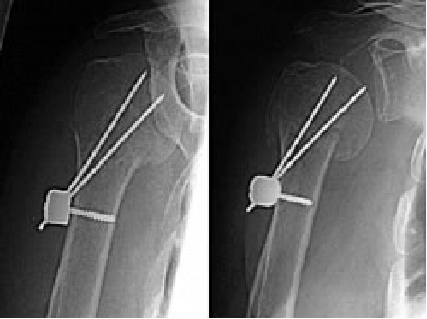

7.微创内固定:

-

Resch Humerusblock(动力固定装置)

关节镜辅助下经皮螺钉固定

微创内固定不足:

骨折移位(Humerusblock better than only Kirschner wire)

骨折不愈合、骨折固定不够牢靠、影响早期功能锻炼

→追求弹性固定、髓内骨折而缺少锁定机制,骨折移位发生率高!